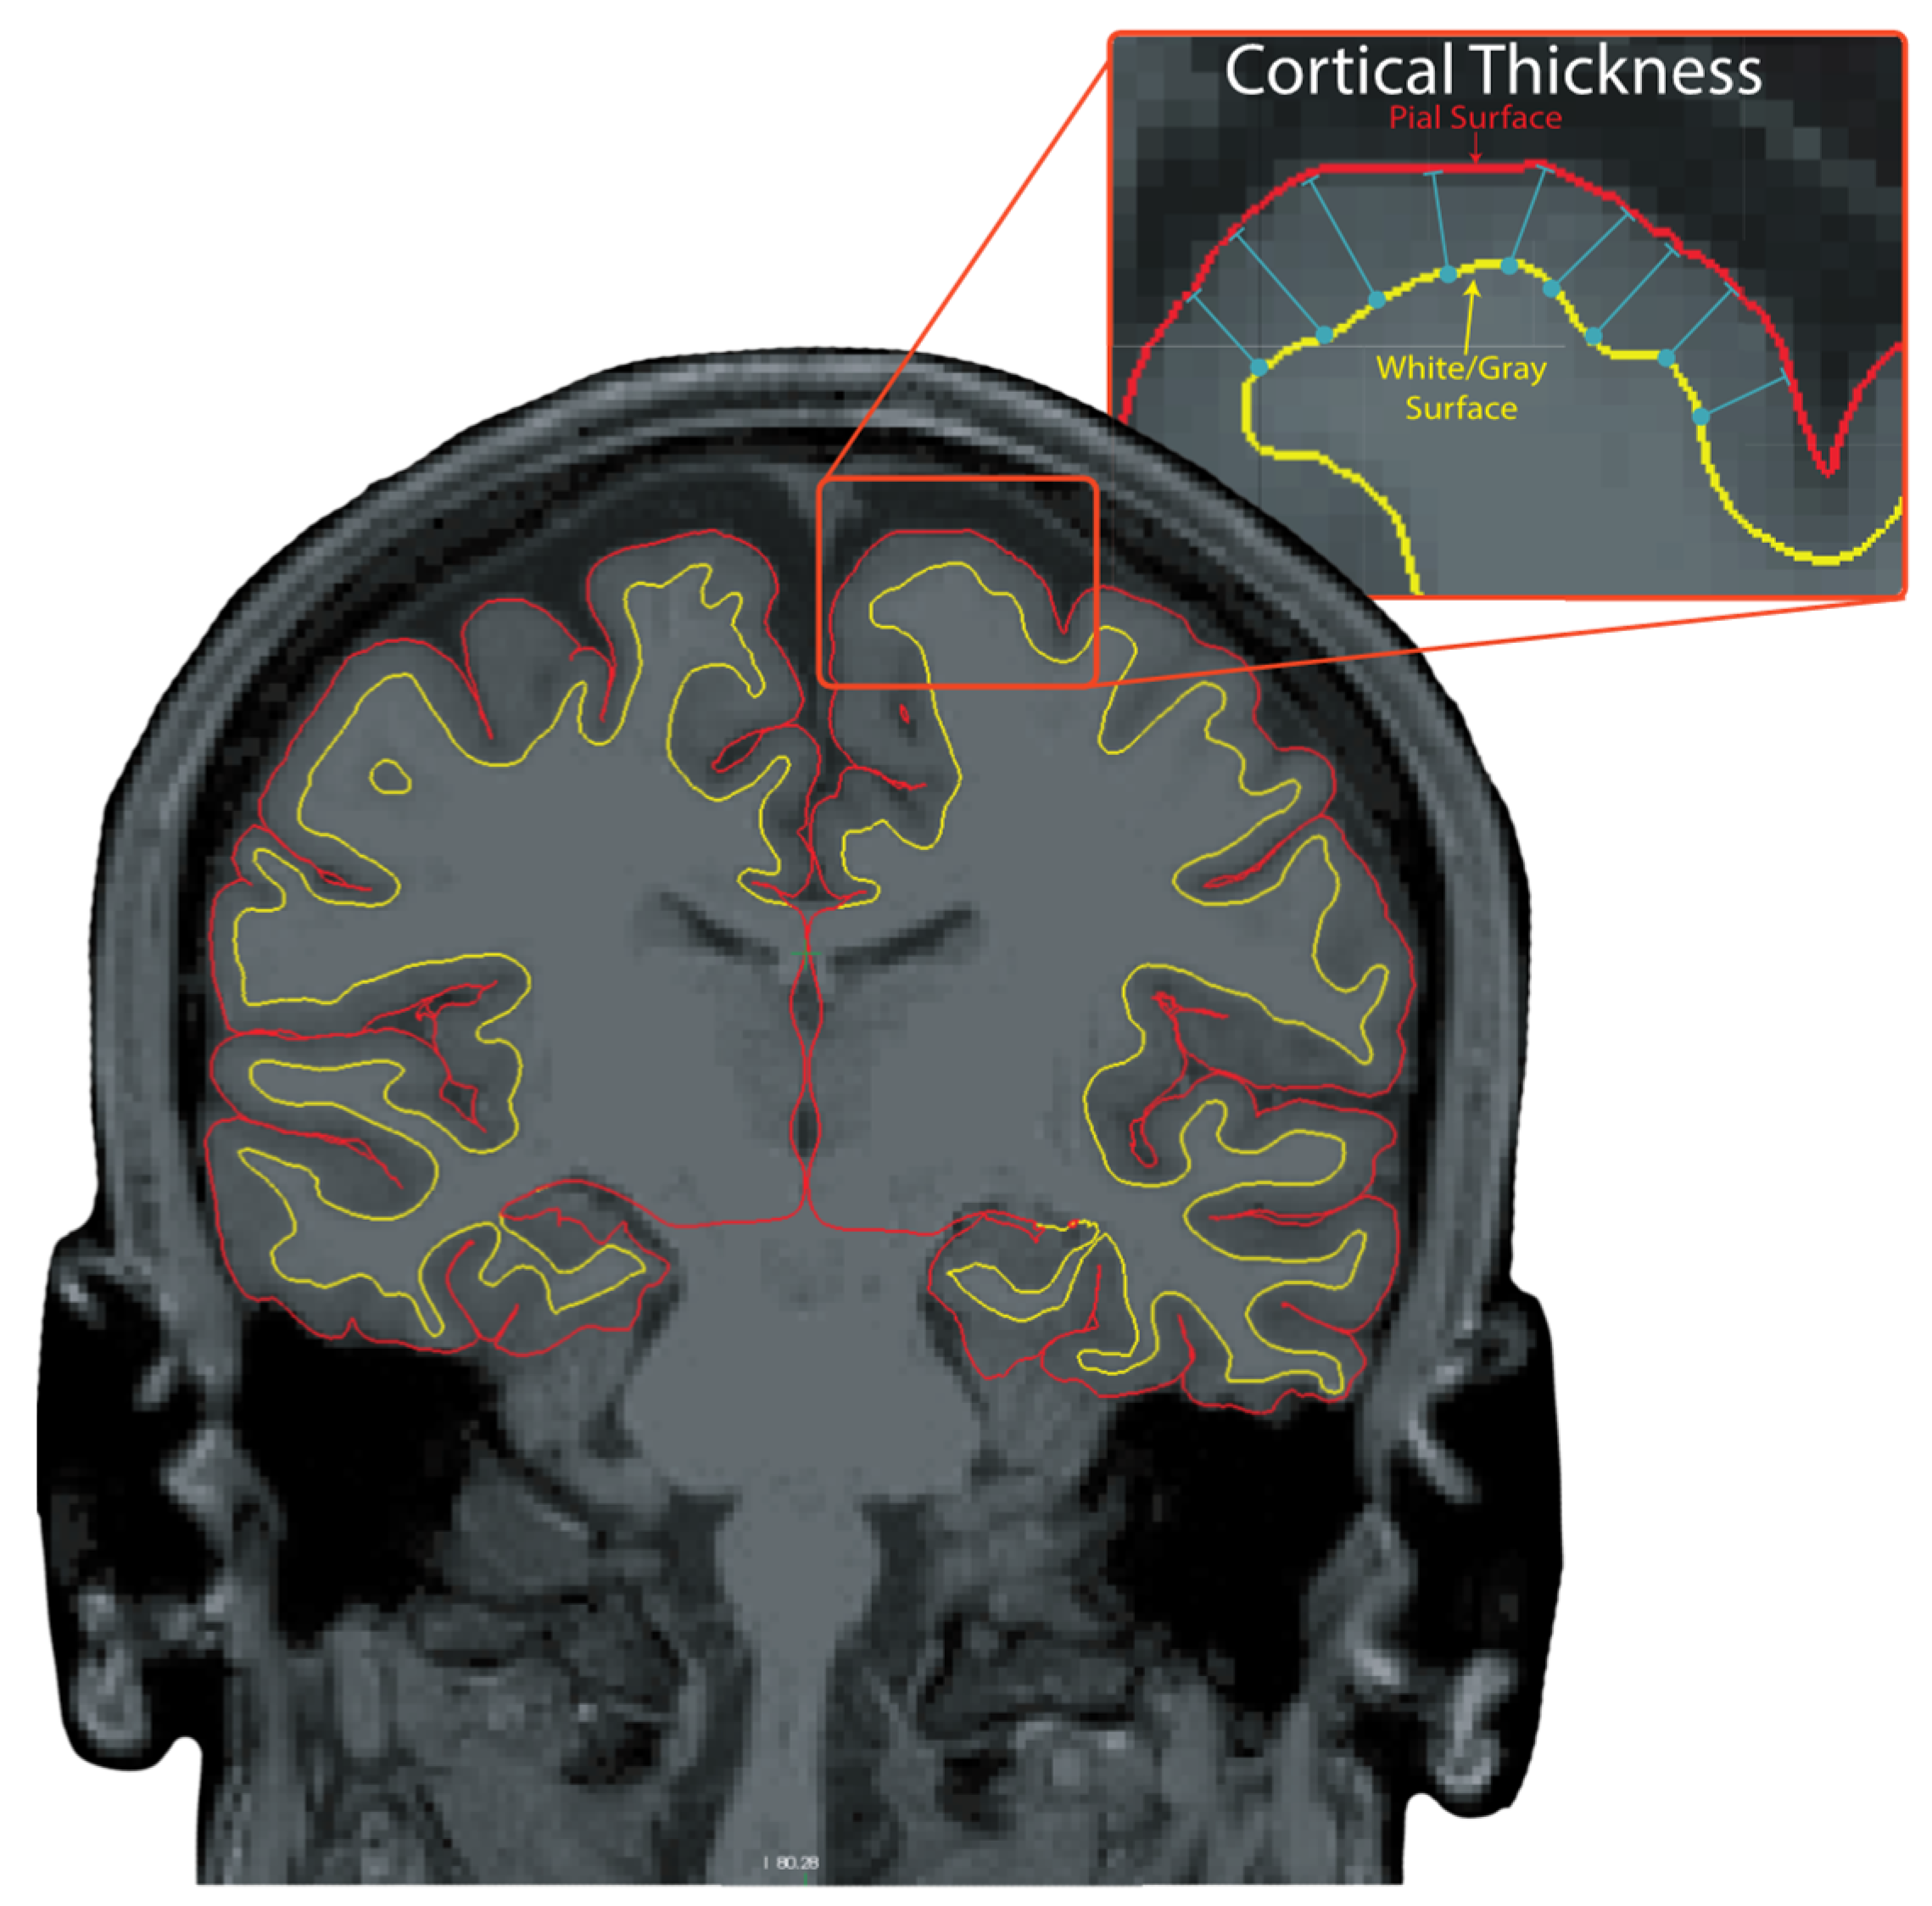

2.5. MRI Processing

- Fischl, B.; Dale, A.M. Measuring the thickness of the human cerebral cortex from magnetic resonance images. Proc. Natl. Acad. Sci. USA 2000, 97, 11050–11055. [Google Scholar] [CrossRef]

- Lindroth, H.; Nair, V.A.; Stanfield, C.; Casey, C.; Mohanty, R.; Wayer, D.; Rowley, P.; Brown, R.; Prabhakaran, V.; Sanders, R.D. Examining the identification of age-related atrophy between T1 and T1 + T2-FLAIR cortical thickness measurements. Sci. Rep. 2019, 9, 11288. [Google Scholar] [CrossRef]

- Fischl, B.; van der Kouwe, A.; Destrieux, C.; Halgren, E.; Segonne, F.; Salat, D.H.; Busa, E.; Seidman, L.J.; Goldstein, J.; Kennedy, D.; et al. Automatically parcellating the human cerebral cortex. Cereb. Cortex 2004, 14, 11–22. [Google Scholar] [CrossRef] [PubMed]